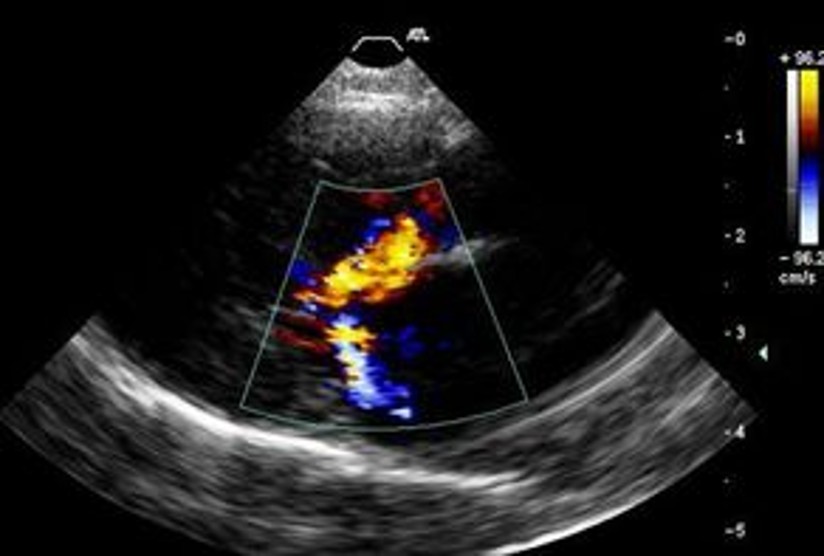

Echocardiography - Doppler echocardiogram with colour flow